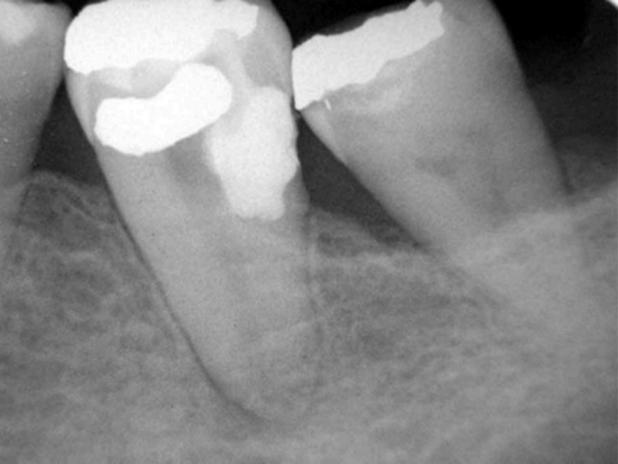

При клиническом осмотре было выявлено, что зуб смещен в мезиальном направлении, вероятно, вследствие потери первого моляра. Зуб реагировал незначительной болезненностью на перкуссию, при этом подвижность была в пределах нормы. На рентгенограмме было обнаружено внутриканальное рентгеноконтрастный материал в дистальной области корня, покрывающее супракрестальную корневую перфорацию (рис. 1). Также была выявлена апикальная радиолюцентность, что свидетельствовало о некрозе пульпы.

Рисунок 1. Периапикальная рентгенограмма, указывающая на супракрестальную перфорацию.